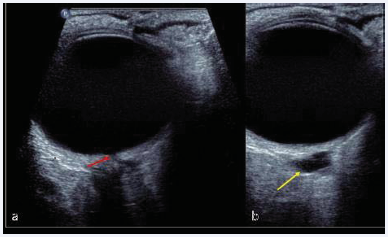

Ultrasound imaging of the orbit, further characterized the ODP measuring at 1.1mm (Figure 2a).

Figure 2 Ultrasound orbit. (a) ODP measuring 1.1mm and linear hypoechoic tract. (b) hypoechoic cyst.

It also shows a linear hypoechoic tract extending from the pit into an irregular hypoechoic cyst (Figure 2b).